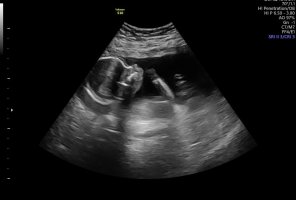

Det beste for å se kjønn nå er et pottyshot, altså et bilde fra rumpa og opp med beina stikkende ut. Hvis jordmor sa gutt så tror jeg dessverre sannsynligheten er ganske stor for at hun har rett. Skjønner du vil ha jente etter så mange gutter, men sannsynligheten øker også litt for å få det samme kjønnet man har om man har flere. Du kan jo ta familien Ingebrigtsen (løpe familien) som et eksempel, de fikk vel 5 gutter før de fikk en jente, så fikk de en gutt til etter den jenta. Så det skjer jo selv om det nok er mer uvanlig.Jeg er uke 18×2dager jeg hva på ultralyd idag jordmor sa det er gutt men jeg er usikker på om det er en gutt eller jenter... her er bilder av baby.. baby hjertet dnker 155

Det viser ikke noe nub på bildene, men jo lenger ut man kommer jo vanskeligere blir det å se kjønn fordi de blir så store at man ikke like lett klarer å se vinkel har jeg hørt, men hvis jordmor sa gutt så er det nok liten sannsynlighet for at det er feil. De sier ikke noe om de er usikre, isåfall sier dem at de er usikre.Så trur du den er en lillegutt eller kan men ta en ny ultralyd litt senere etter uke 25